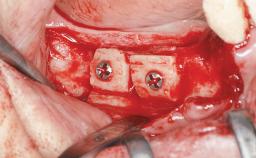

Guided Bone Regeneration (GBR) with a Particulated Autologous Graft and a ePTFE-Reinforced Membrane for Vertical Augmentation of a Single-Tooth Edentulous Space in the Esthetic Zone

A 47-year-old Caucasian woman with a single-tooth edentulous space at the site of the left maxillary canine was referred for treatment. She had undergone traumatic extraction of this impacted canine several months before referral. Her chief complaint was the dissatisfying appearance of her smile. The patient desired a stable and esthetic rehabilitation of the site. Her dental history showed no evidence of periodontal disease or bruxism. She had no systemic diseases, was not taking any medications, and did not smoke. The extraoral examination revealed a high lip line and an inadequate soft-tissue volume at the defective canine site. Large black triangles were visible between the canine and its adjacent teeth.

Bone Augmentation Staged|Vertical

Augmentation Materials Autogenous chips|Membrane